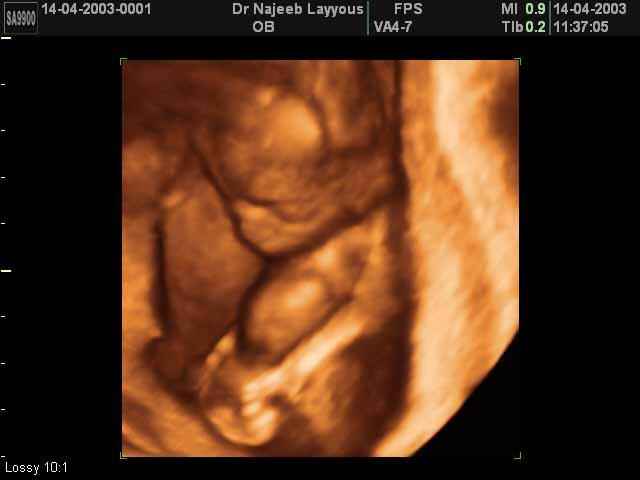

- Fetal Behavior Ultrasound Photos

3D Second Trimester Ultrasound Scan Photos-second part of pregnancy | Dr N Layyous